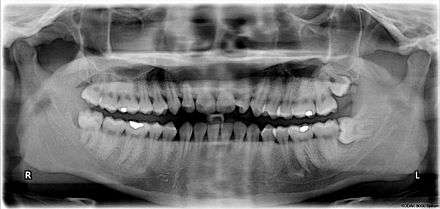

The upper left (picture right) and upper right (picture left) wisdom teeth are distoangularly impacted. The lower left wisdom tooth is horizontally impacted. The lower right wisdom tooth is vertically impacted (unidentifiable in orthopantomogram).